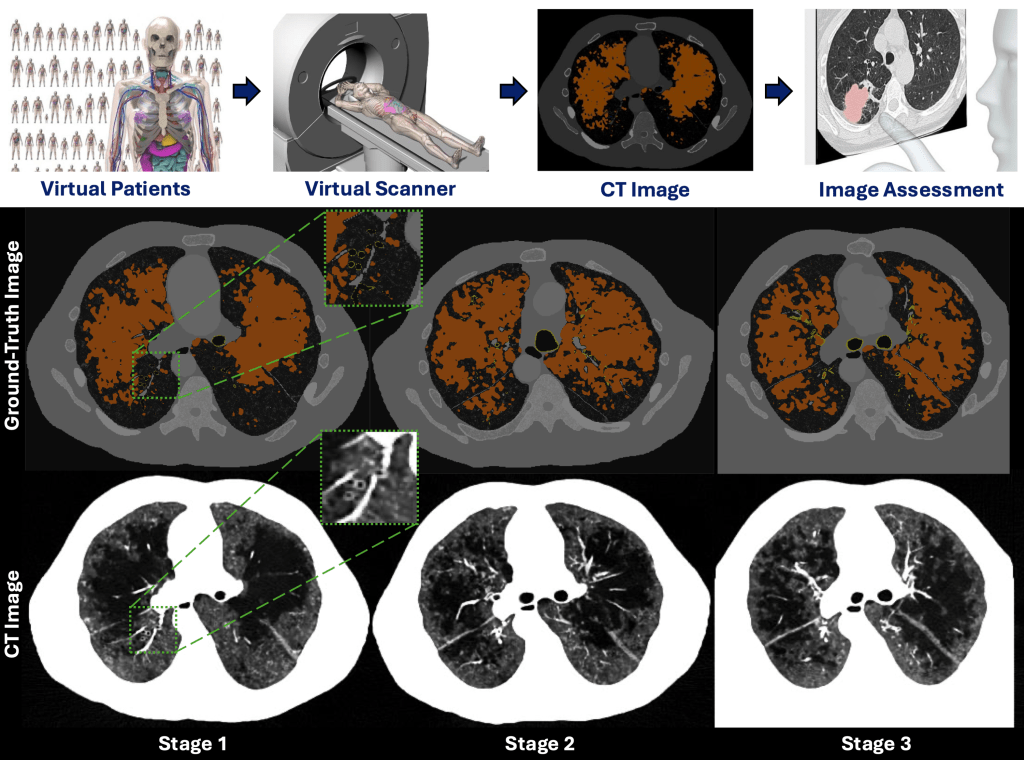

Using virtual/in-silico imaging trials with digital twins to assess the quantitative performance of CT scanners and acquisition protocols for COPD (emphysema and bronchitis) biomarkers, ensuring accuracy and consistency in both cross-sectional and longitudinal evaluations.

Chronic obstructive pulmonary disease (COPD) is a major cause of death in the US, characterized by emphysema and bronchitis. Bronchitis is the inflammation of the bronchial tubes (airways), and airway measurements using quantitative CT can provide an objective assessment of bronchitis severity. However, the accuracy of this measurement is limited by the spatial resolution and image noise of the CT imaging systems. The emerging photon-counting CT (PCCT) technology has the potential to improve airway quantification due to its superior noise and spatial resolution performance. To quantify its benefits, it is important to do a systematic task-specific evaluation of PCCT against energy-integrating CT (EICT) for airway measurements. However, conducting such studies on real patients is not cost-effective and has ethical limitations as well. Additionally, acquiring ground-truth information from patient images is also not feasible, which is required to measure the degradation caused by the scanner or the imaging parameters. The virtual imaging trial framework can simulate real CT scanning of anthropomorphic-computational human phantoms (XCAT) with varying severity of bronchitis. This framework was used in this study to compare the quantitative performance of deep silicon-based PCCT with conventional EICT for airway measurements and identify the optimal CT imaging parameters for accurate bronchitis quantification.